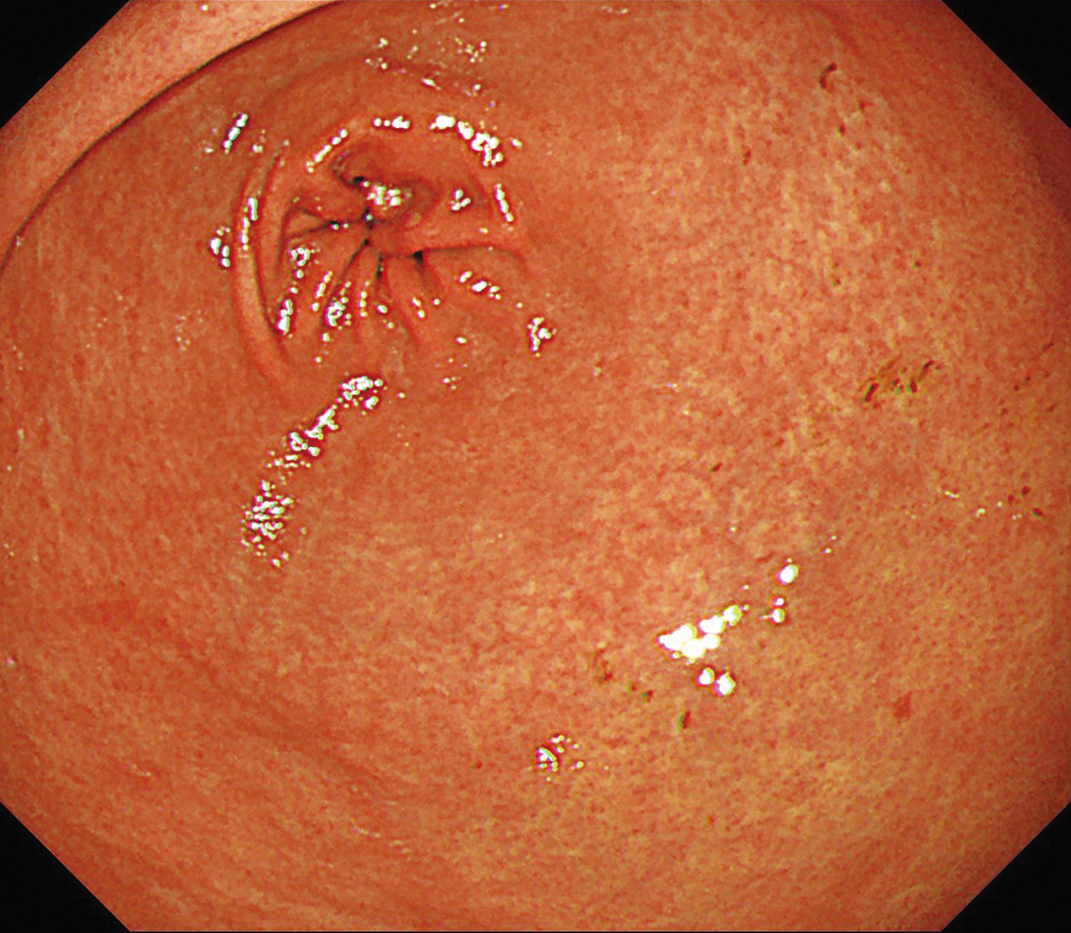

EVIS X1×GIF-1200N 症例画像

胃角部小弯